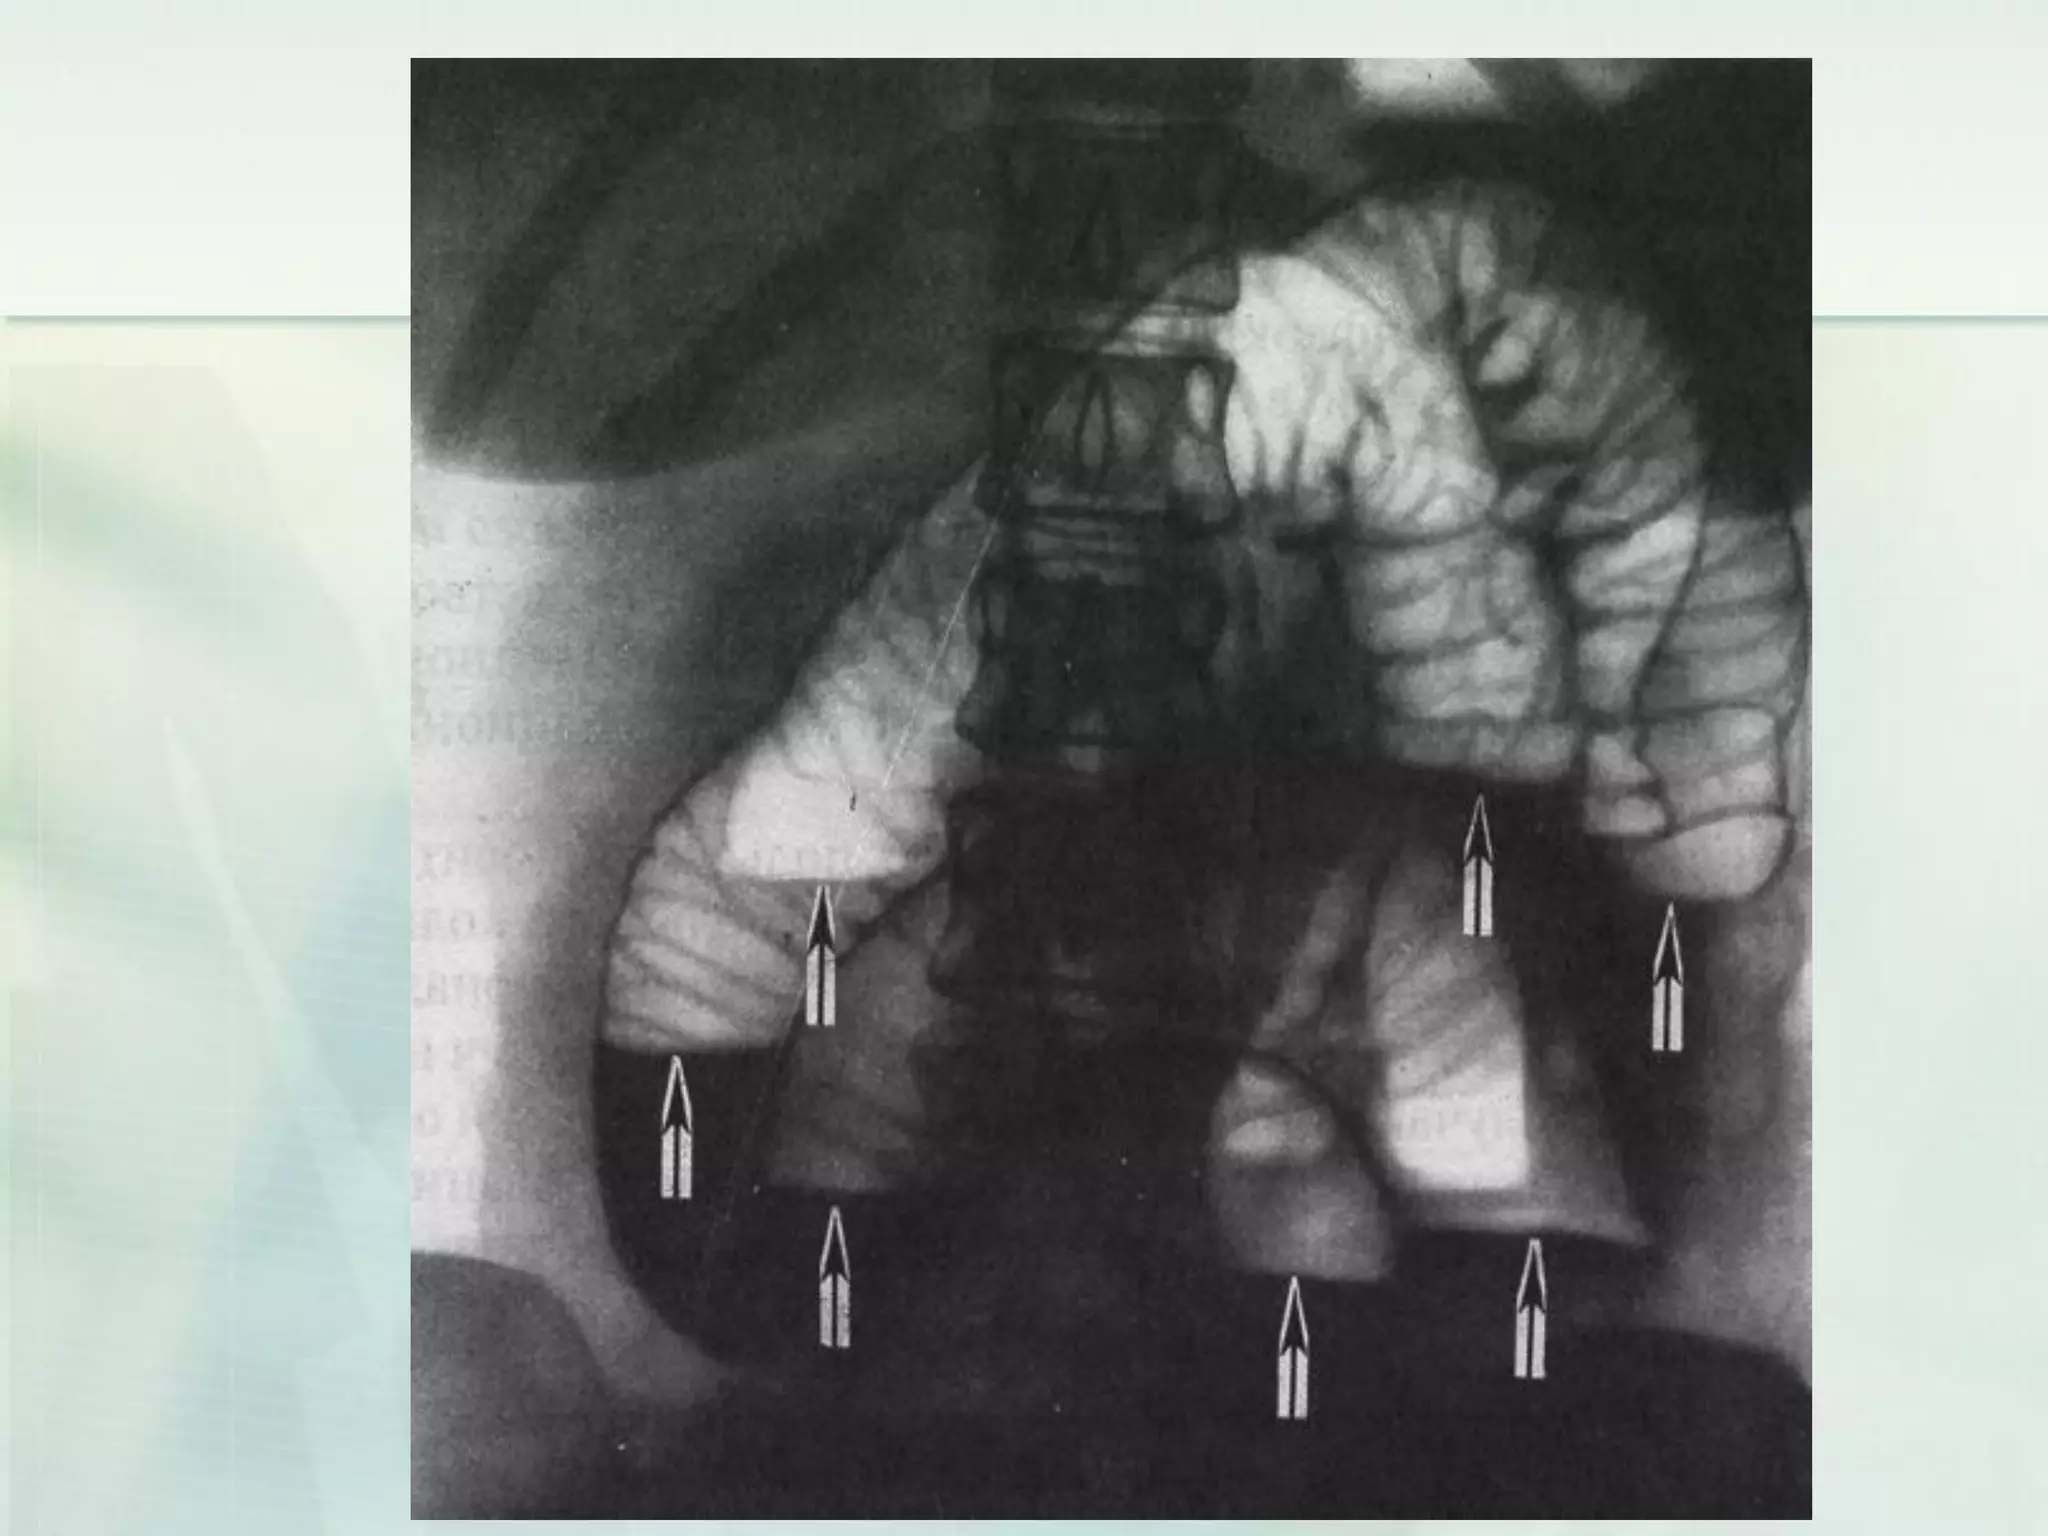

CT scan of a small bowel

obstruction

Laboratory investigations (Small bowelobstruction)  Computed tomography (CT) is playing a growing role in the diagnosis of intestinal obstruction.  Signs of obstruction by CT scan include proximal dilatation with transition point and closed-loop obstruction with a 'beak' sign.  Small bowel strangulation can be shown as circumferential thickening of the bowel wall, increased small bowel attenuation, pneumatosis, and 'target sign' secondary to thickening.

CT scan ofa small bowel obstruction